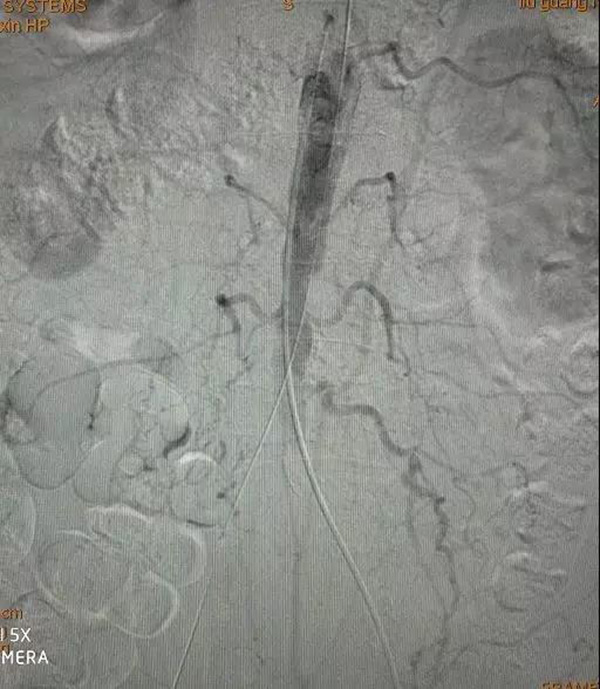

術(shù)中開通右側(cè)髂動脈后造影顯示腹主動脈狹窄

以同樣方法開通左側(cè)髂動脈

逆行造影顯示左髂動脈狹窄

雙側(cè)均以6mm-120mm球囊擴張

置入腹主動脈支架

雙髂動脈支架植入

支架全部置入后血流重新建立